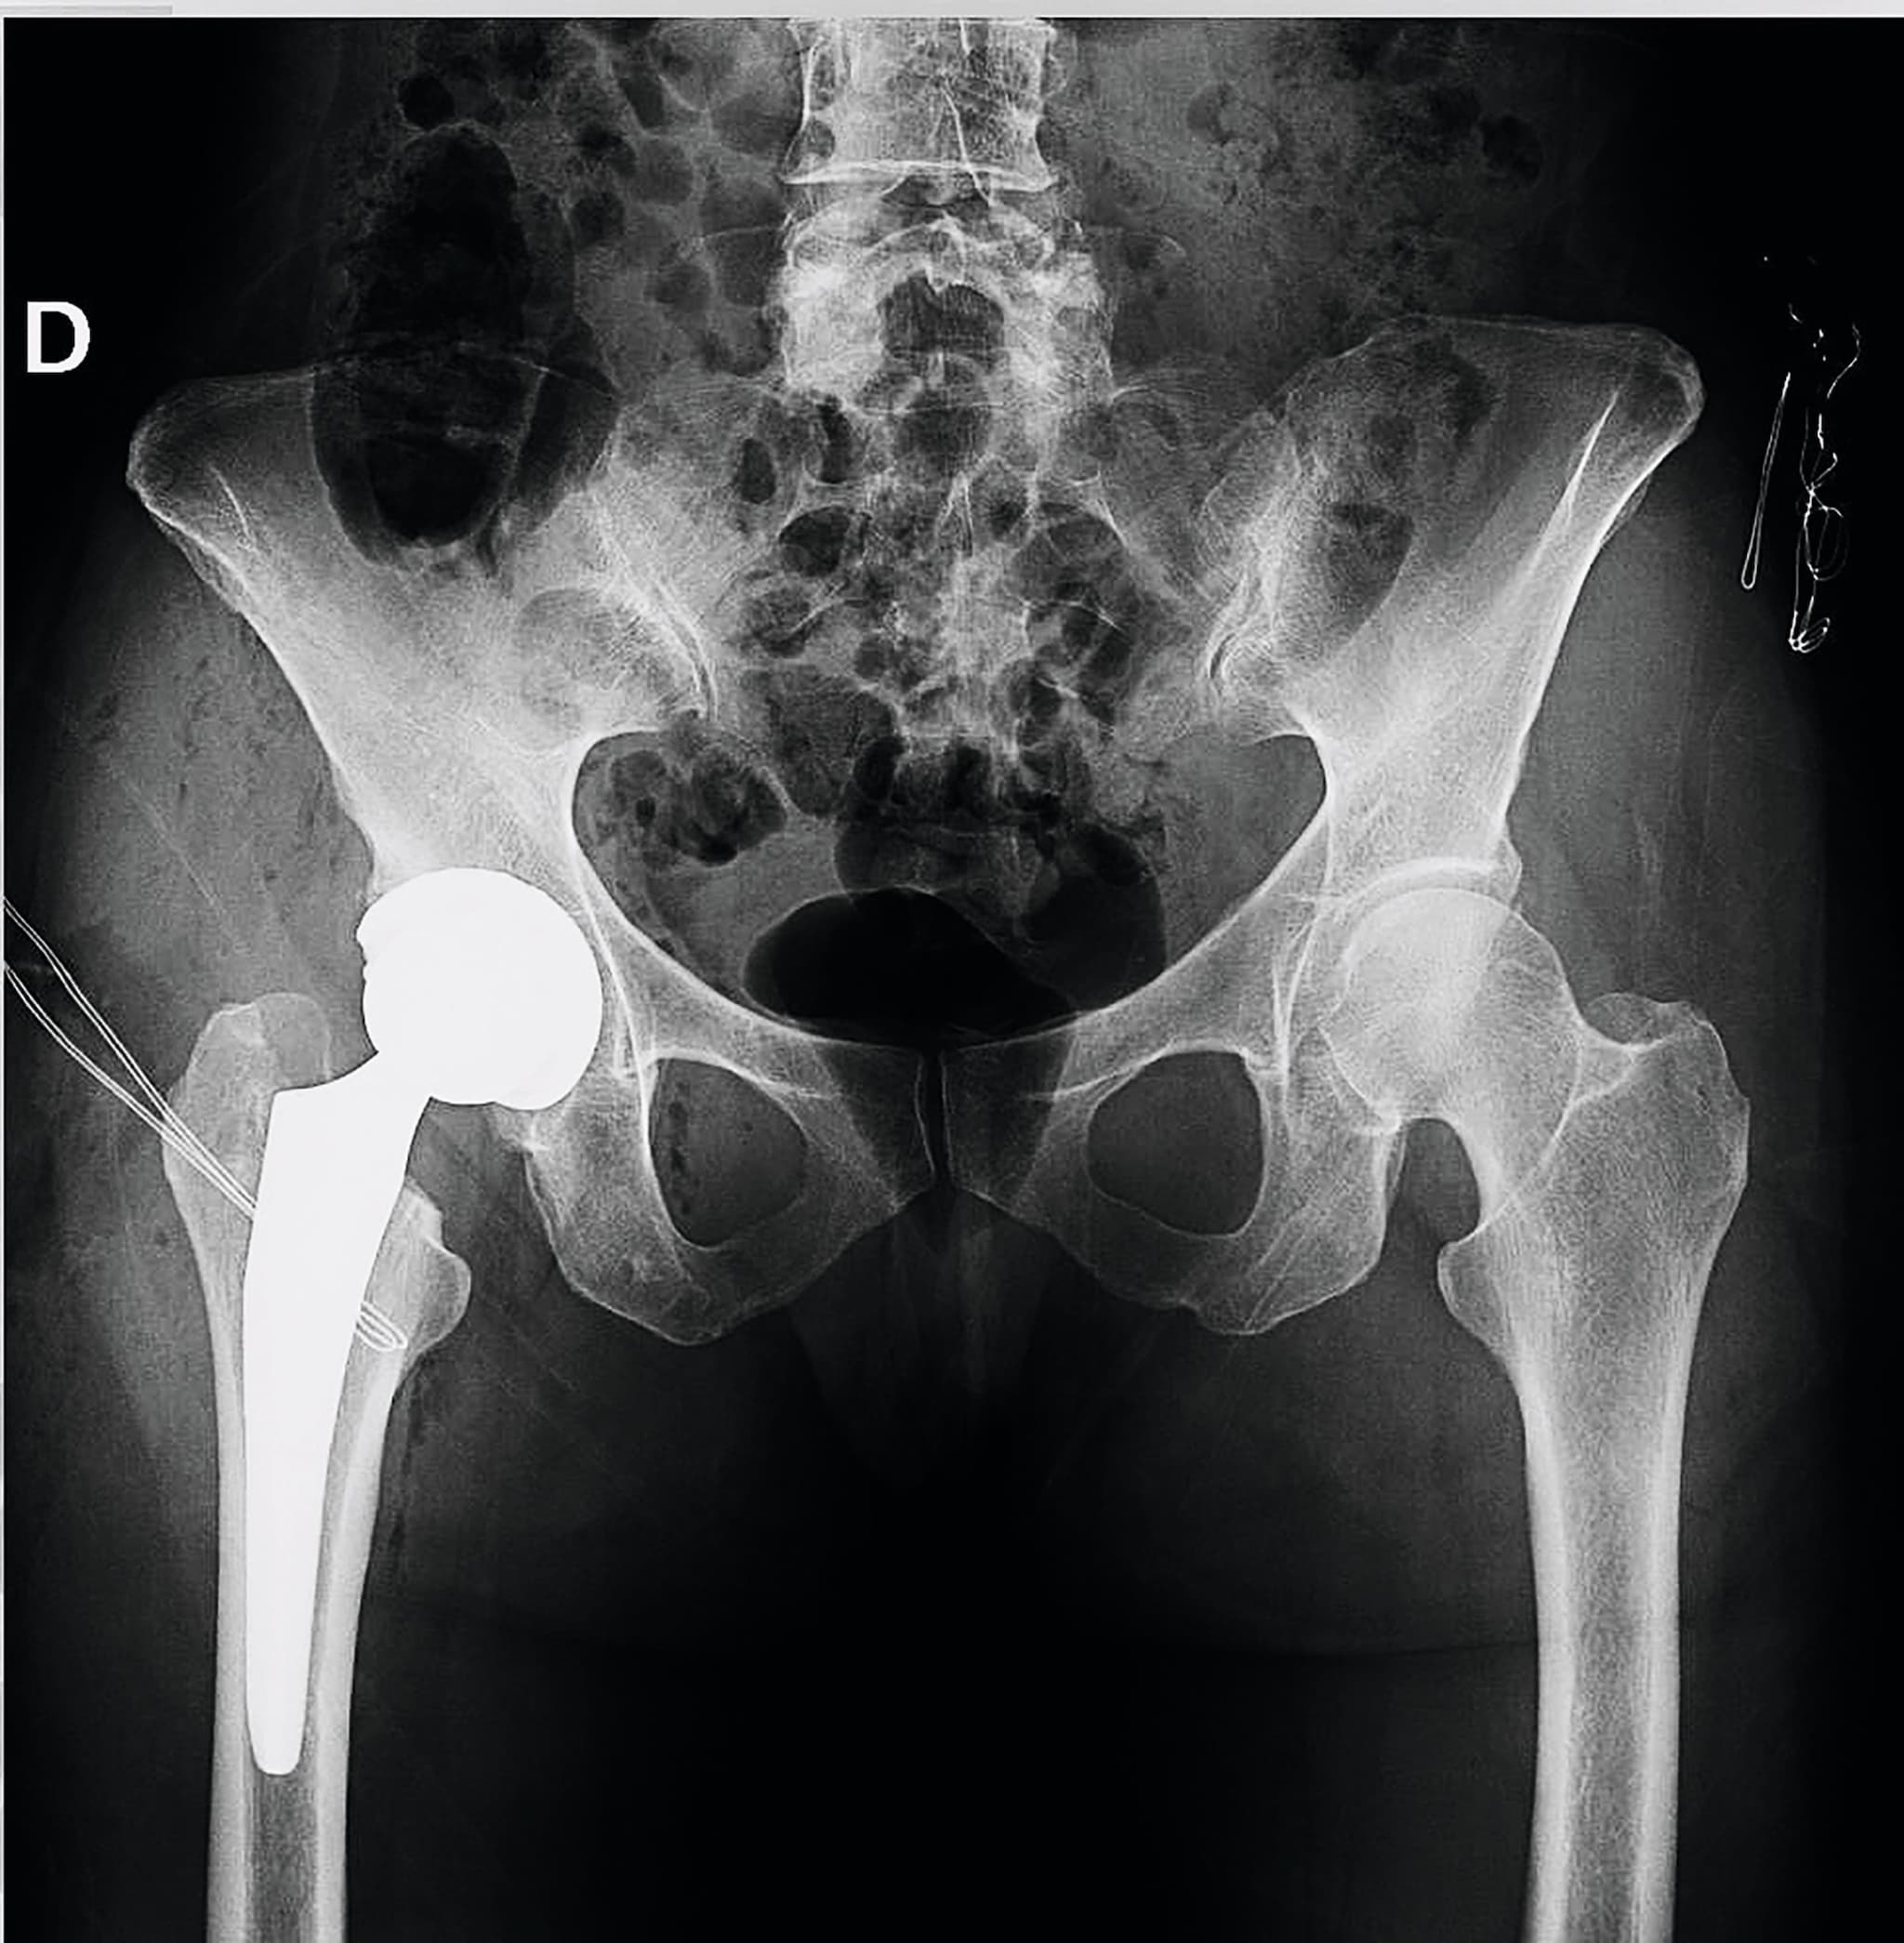

La modelo y empresaria contaba que había tenido que someterse a una operación de cadera para que le pusieran una prótesis de titanio y rompía su silencio sobre la difícil situación a la que lleva tiempo enfrentándose: sufre artrosis severa y esta enfermedad estaba afectando a su día a día. Ahora ha llegado el momento de parar, de escuchar a su cuerpo, cuidarse y también dejarse cuidar por su familia, mientras afronta esta nueva etapa.

Me han colocado una prótesis de titanio en la cadera. Es una cirugía importante, pero necesaria para recuperar movilidad y reducir el dolor. Estoy muy agradecida al equipo médico por cómo me han cuidado.